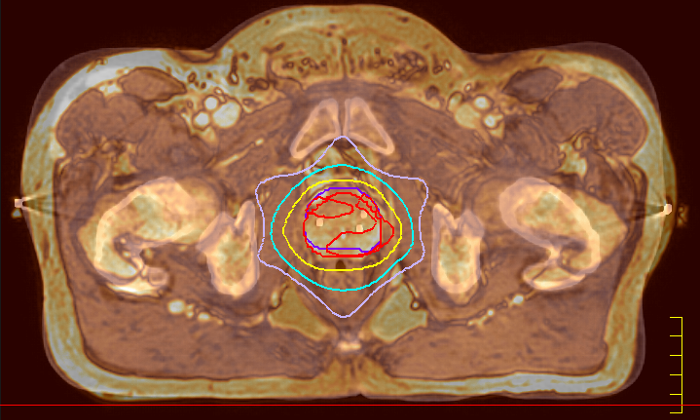

Innovative MR-only simulation helps you use MRI as the primary imaging modality for planning prostate cancer patients’ treatment, thereby eliminating tedious and error-prone CT-MR registration and simplifying workflows. Available as a plug-in extension to the Ingenia MR-RT platform, MR-only simulation provides high contrast anatomical MR images for target delineation and the density information for dose calculations typically provided by CT.

RTdrive is an automated workflow solution that streamlines the process from MR imaging to a high quality treatment plan with minimal user input, thus accelerating time to treatment and driving consistency. RTdrive accelerates and automates prostate planning workflows, enabling you to create a treatment plan within 25 minutes* from the start of MR simulation.